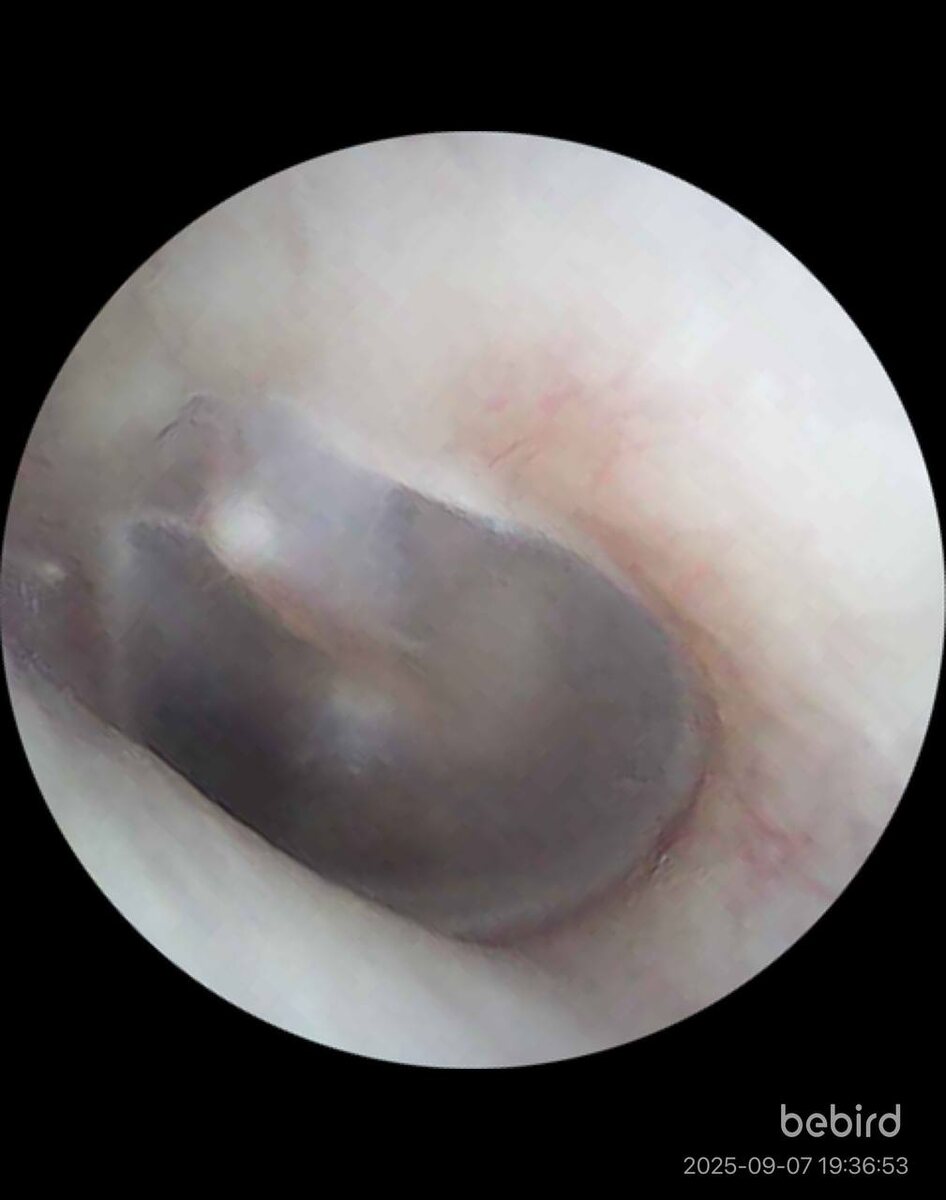

Вот так выглядит барабанная перепонка при жидкости в среднем ухе ребёнка из-за аденоидов. Фото 1.

📌Нормальная барабанная перепонка. Фото 2